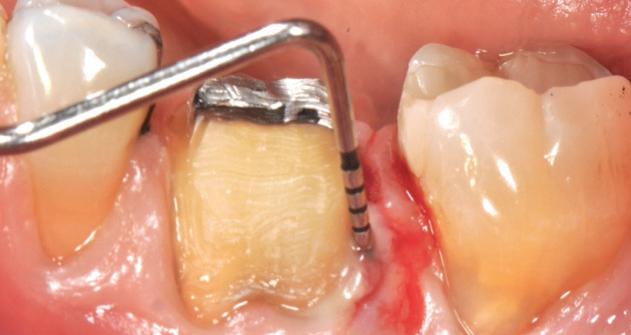

year old female patient presented with clinical and radiographic evidence of an mm.

The crown was biologically shaped and the root detoxified using Ellman burs. After flap opening and complete defect debridement, GEM S® was used to fill the defect.

The graft was then covered with Geistlich Bio-Gide®.

year old female patient presented with clinical and radiographic evidence of an mm

Base line

F l ap re fle c tio n sh o wing the d o n the dis t al o ≥ m m poc ket d epth